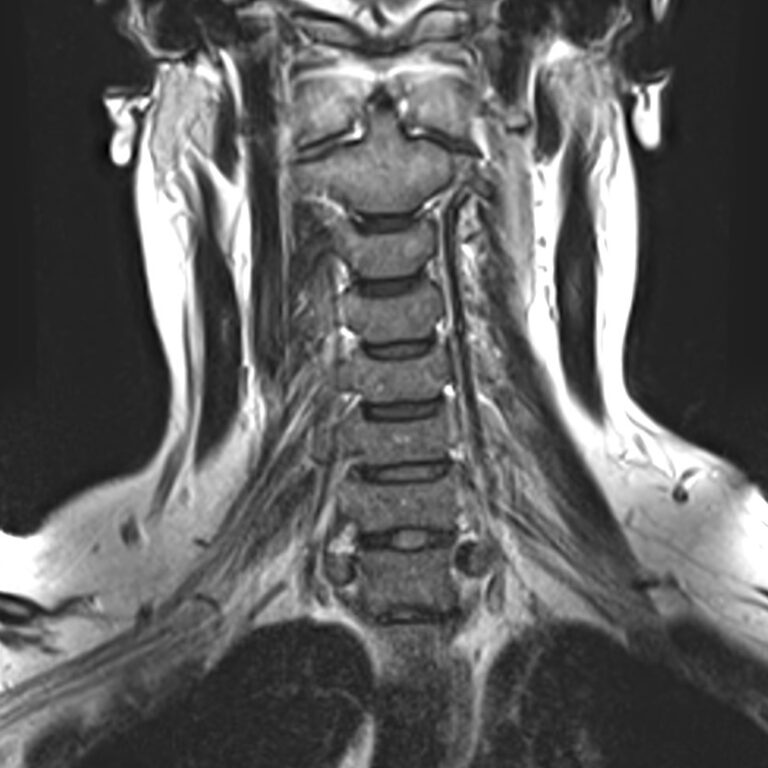

Для того, чтобы оценить состояние шейных позвонков с прилегающими тканями и одновременно визуализировать плечевой сустав, в нашей клинике выполняется комплексное обследование, включающее два протокола: МРТ шейного отдела позвоночника и МРТ плечевого сустава.

Метод МРТ позволяет оценить состояние всех анатомических областей шейного отдела позвоночника: костную структуру позвонков, спинной мозг с отходящими от него нервными корешками и окружающие мягкие ткани. Протокол обследования плечевого сустава включает оценку костной структуры, суставной капсулы, полости сустава с выстилающей его синовиальной оболочкой, связок, сухожилий, мышц и окружающих мягких тканей.